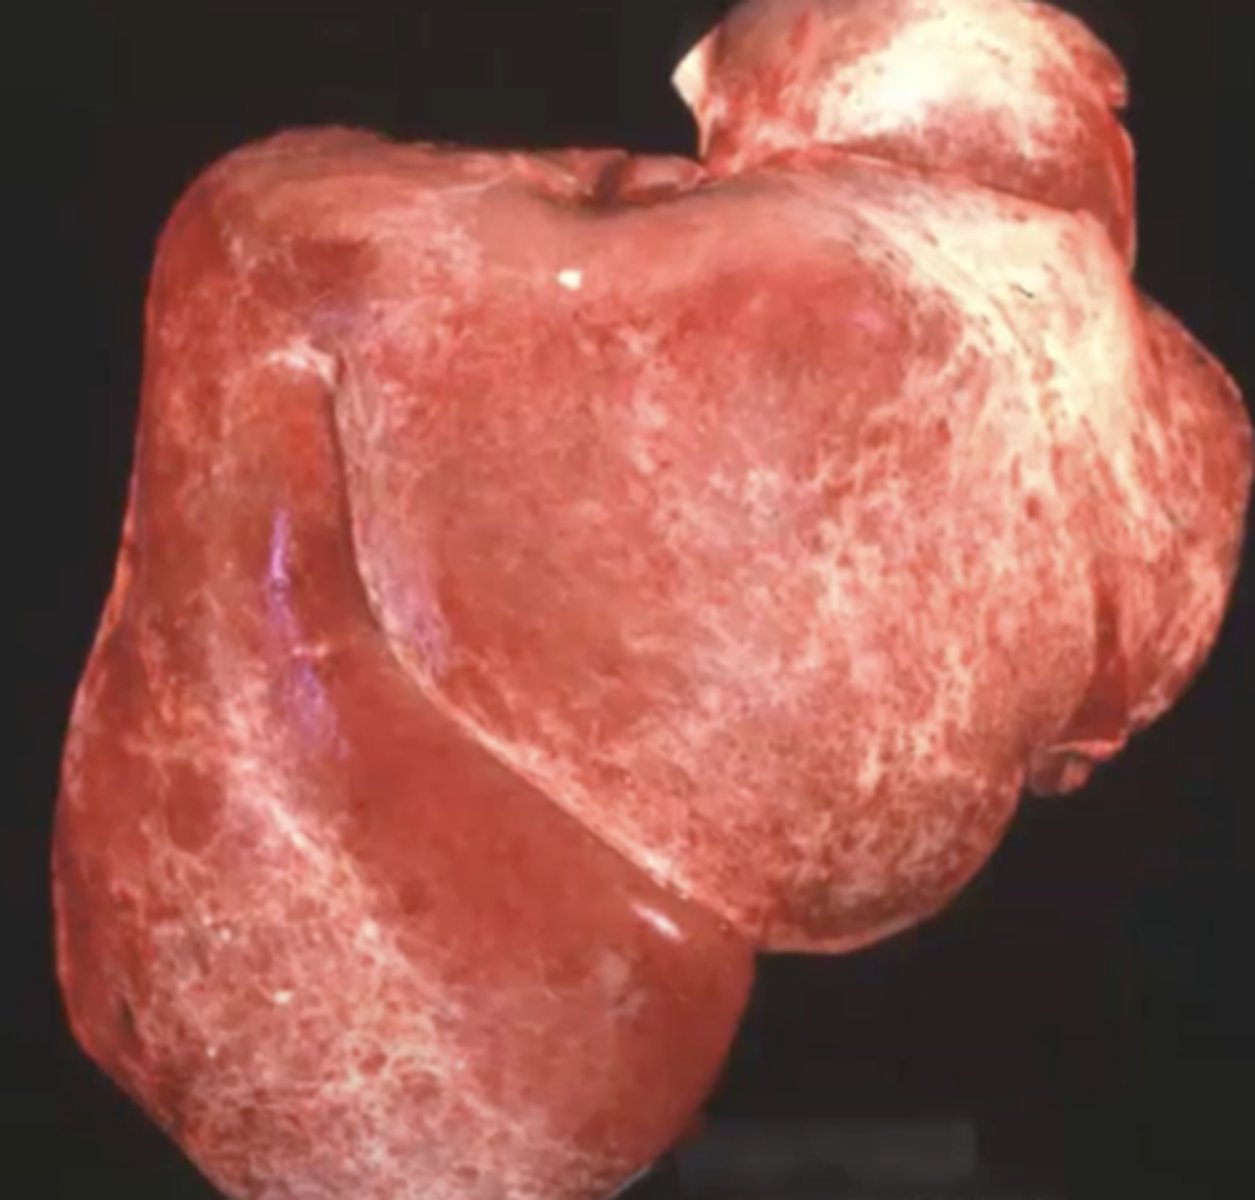

Amyloidosis

-red lines are from rib impressions

-caused by inflammation

What has caused this gross appearance of this liver?